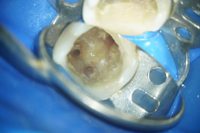

歯の中の画像

歯の根にこびりついている古い充填物や細菌を機械的に除去していきます。顕微鏡を用いることで、複雑な根や見つけづらい細い根の見落としを大幅に減らすことが出来ます。

むし歯や細菌を機械的に取り除き、細かい場所は消毒薬で洗浄し、可能な限り細菌の数を減らします。